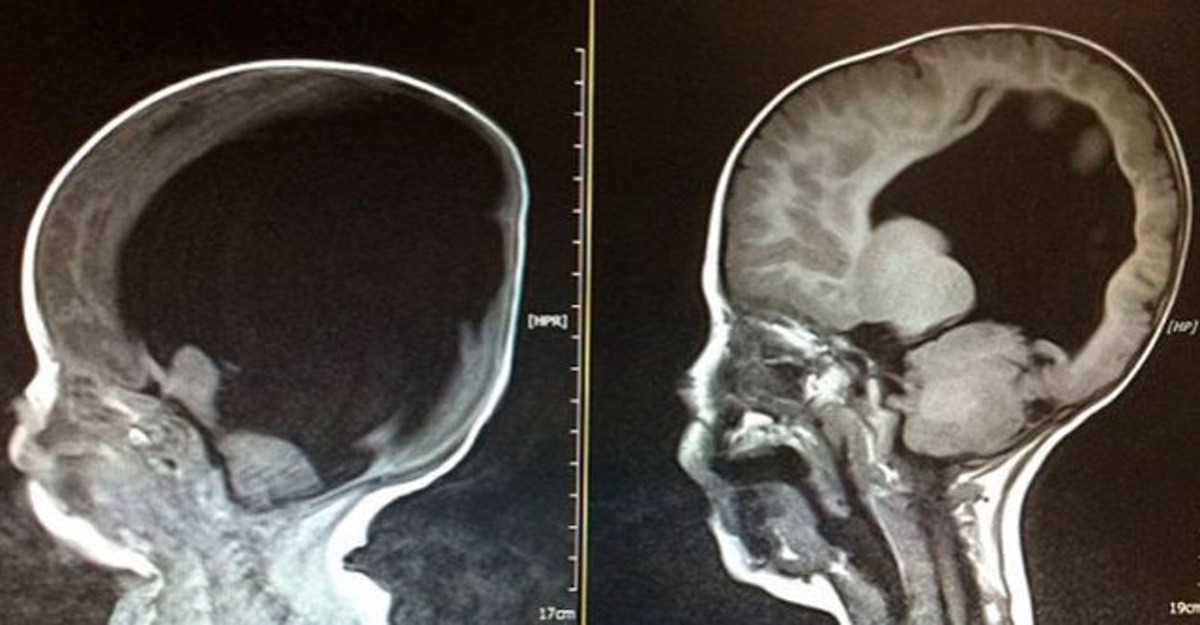

Ce scanner montre une taille de sillons relativement normale mais des ventricules significativement dilatés titre Un patient est amené au service des urgences après une collision arrière avec un. En fait, pour scanners réalisés avant l'âge de 10 ans, on risque de voir se développer un cas de leucémie et un cas de tumeur cérébrale dus aux rayonnements dans les dix années. 11 janv 15 Imagerie numérisée Voir plus d'idées sur le thème radiologie, radiologie médicale, chambre hôpital.

Un Scanner Cerebral A Revele Qu Un Universitaire N Avait Pas De Cerveau Sa Tete Etait Pleine D Eau Upsocl